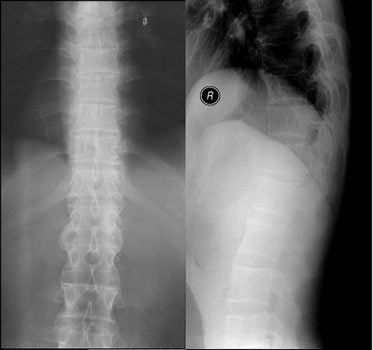

(图:蔡先生的CT检查显示,脊柱弯曲,关节间隙变窄)

医学辅助检查:血常规:白细胞(WBC)7.2X109/L 血红蛋白(Hb)130g/L 血小板(PLT)321X109/L 血沉(ESR)98mm/h C反应蛋白(CRP)34mg/L 免疫球蛋白 IgG 18.83g/L,尿常规尿潜血(BLD)(±);肝功能、肾功能、电解质均正常,CT检查:脊柱关节面有虫蚀样破坏,模糊,脊柱弯曲,关节间隙变窄。